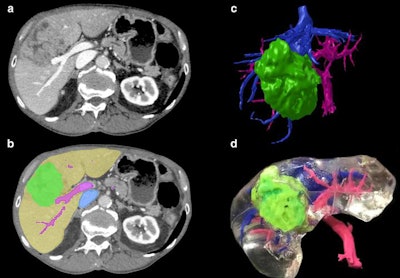

The creation of a 3D-printed liver begins with axial CT scan acquisition (a), followed by image segmentation (b), volume rendering (c), and finally 3D printing (d). Image courtesy of Witowski et al. Licensed under CC BY-NC 4.0.Laparoscopic liver resection is often preferred for its association with reduced patient blood loss and morbidity, but the technique offers clinicians a relatively unnatural view of patient anatomy and no tactile sensation during the procedure. In response, several groups have recently begun recommending the use of intraoperative ultrasound to help guide this procedure.

The researchers segmented and processed the CT scans using open-source software (3D Slicer) and then created multicolor 3D-printed livers using polylactic acid filaments and a 3D printer (Ultimaker 2+, Ultimaker). The entire production sequence, from imaging to silicone casting, took roughly five days (Eur Radiol, November 26, 2019).